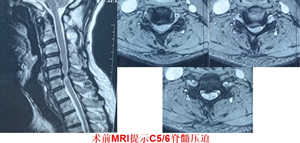

这个病人刚来门诊说他头晕了半年多,最近半个月脖子和肩膀也开始不舒服了。看他走路很僵硬,就简单查了下体,结果右腿肌张力高,右侧上肢病理征阳性,右侧腱反射也增高。再看了看他的检查结果——脊髓型颈椎病!

那这肯定要手术治疗!再跟病人一聊发现这个60多的老爷爷还是越战老兵,那一定得好好整,整的好好地!